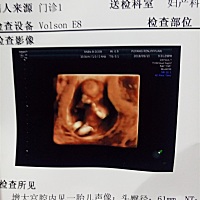

宝贝真棒NT通过

是女孩吗👧、